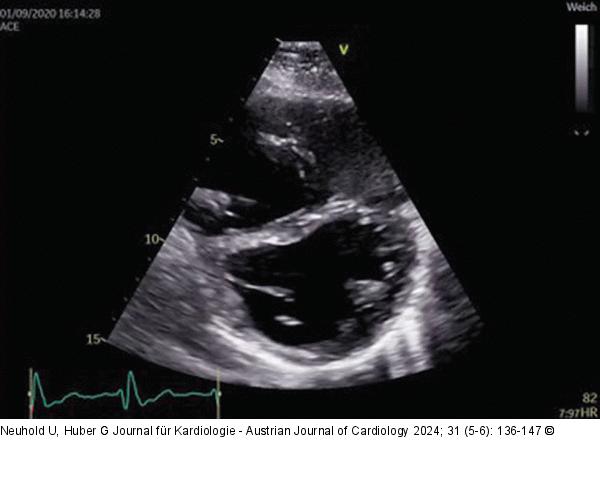

Abbildung 3: Echo Patient mit rechtsventrikulärer Volumsbelastung bei schwerer Trikuspidalinsuffizienz. |

Patient mit rechtsventrikulärer Volumsbelastung bei schwerer Trikuspidalinsuffizienz. |